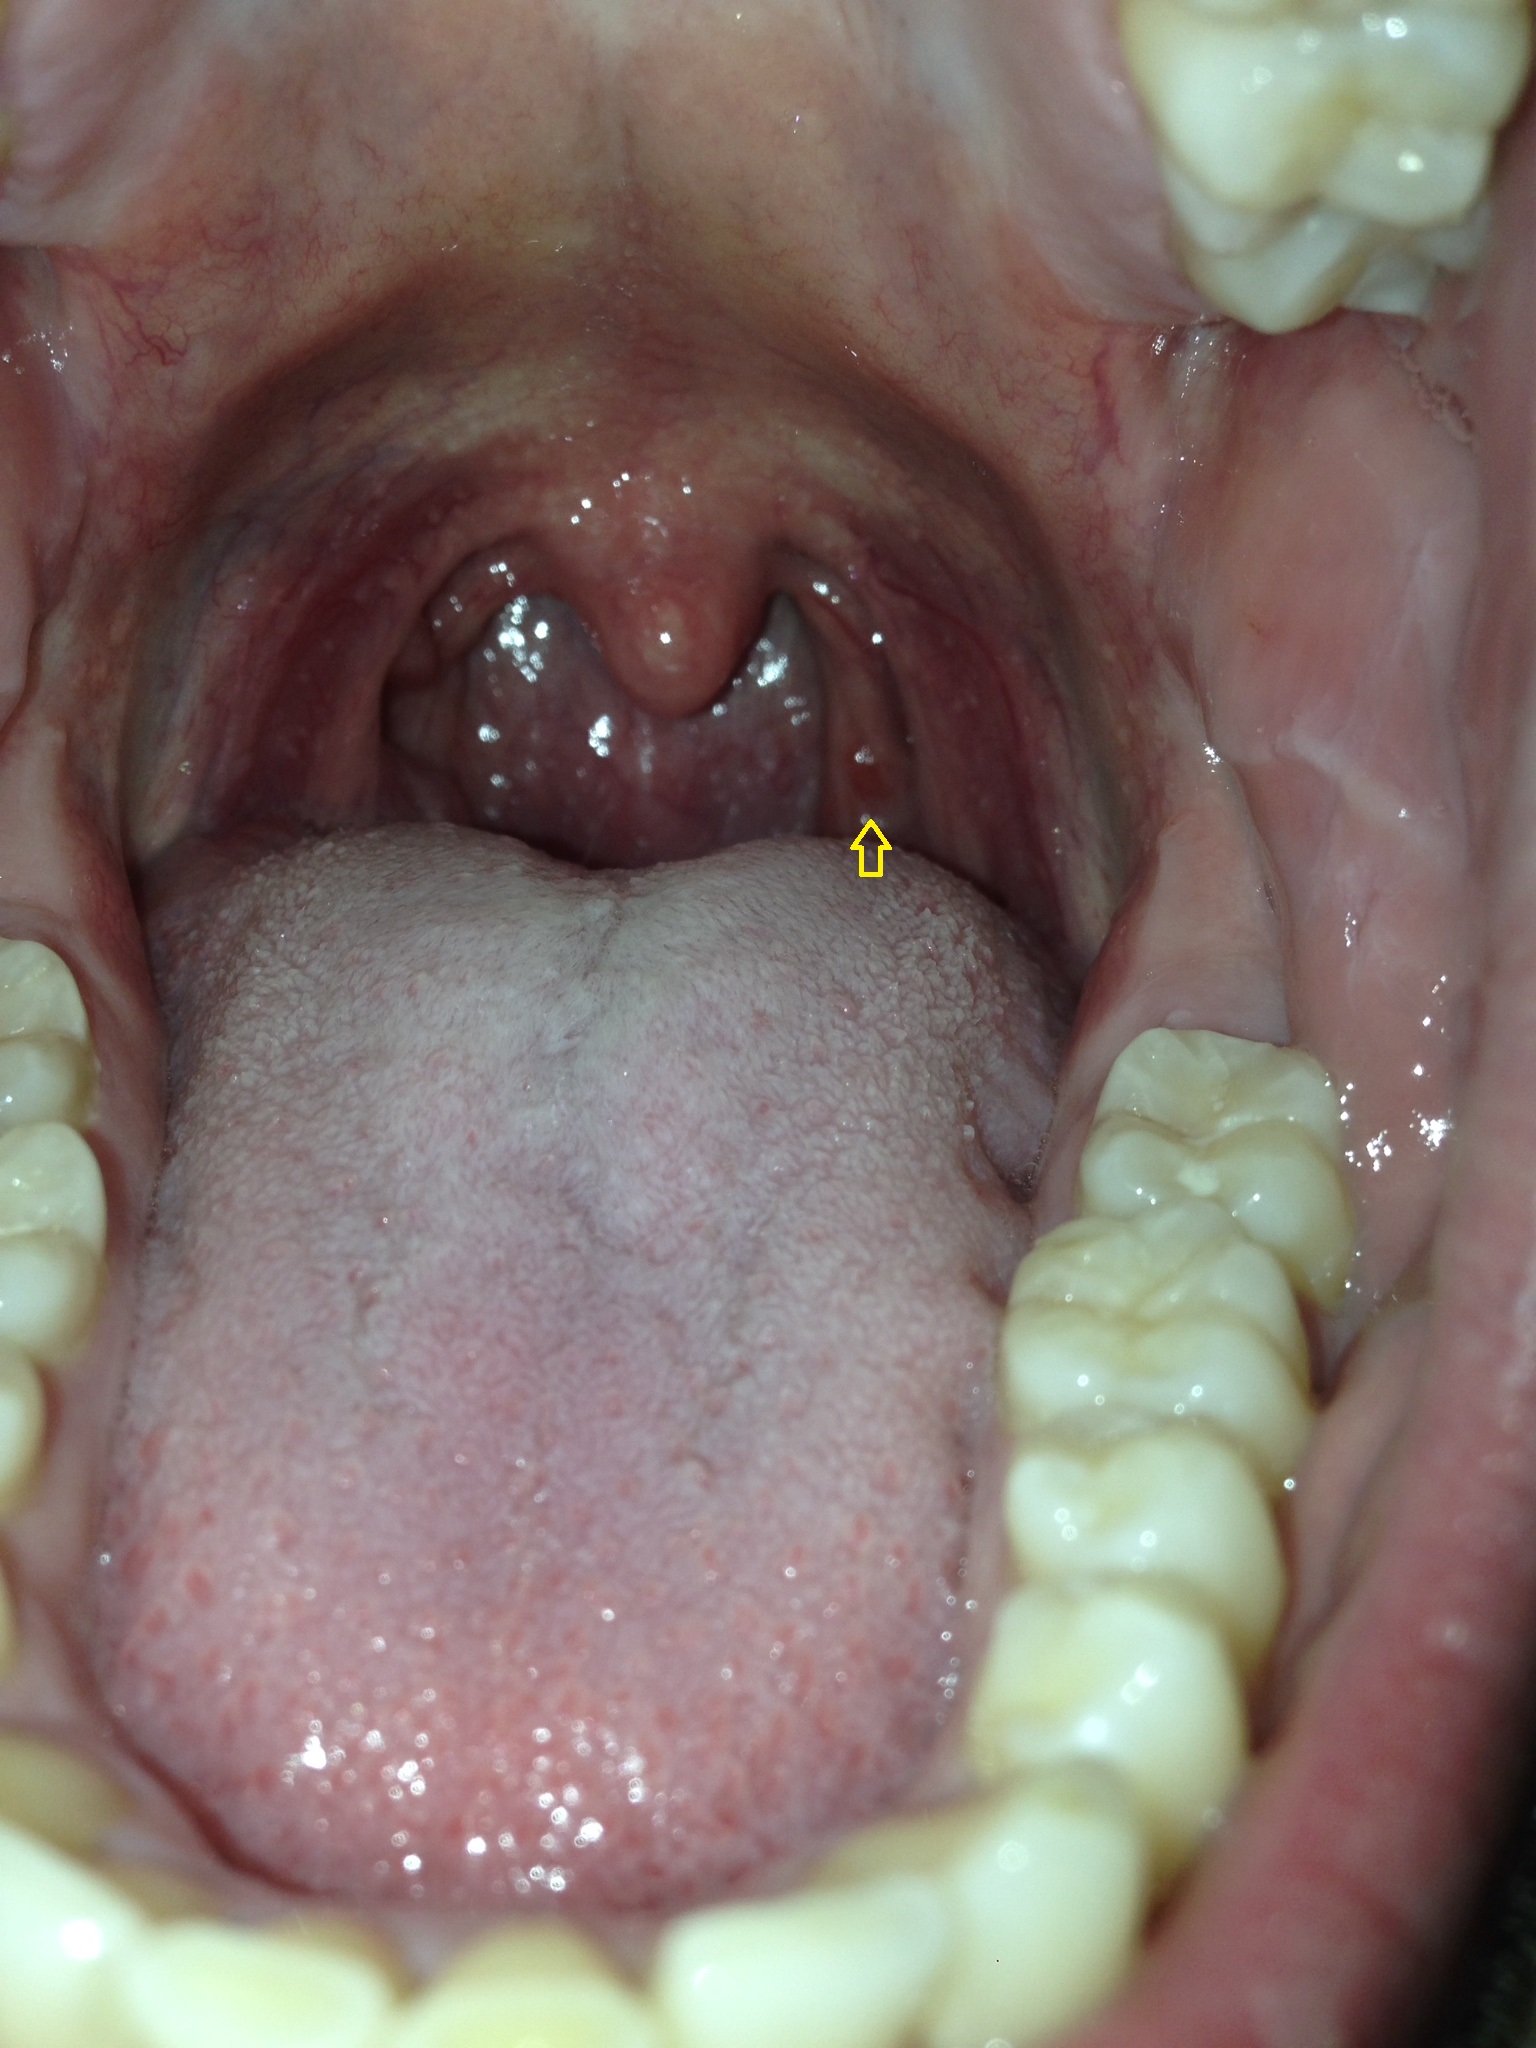

Was ist das für ein roter Punkt im Rachen? (Medizin, Arzt, Hals)